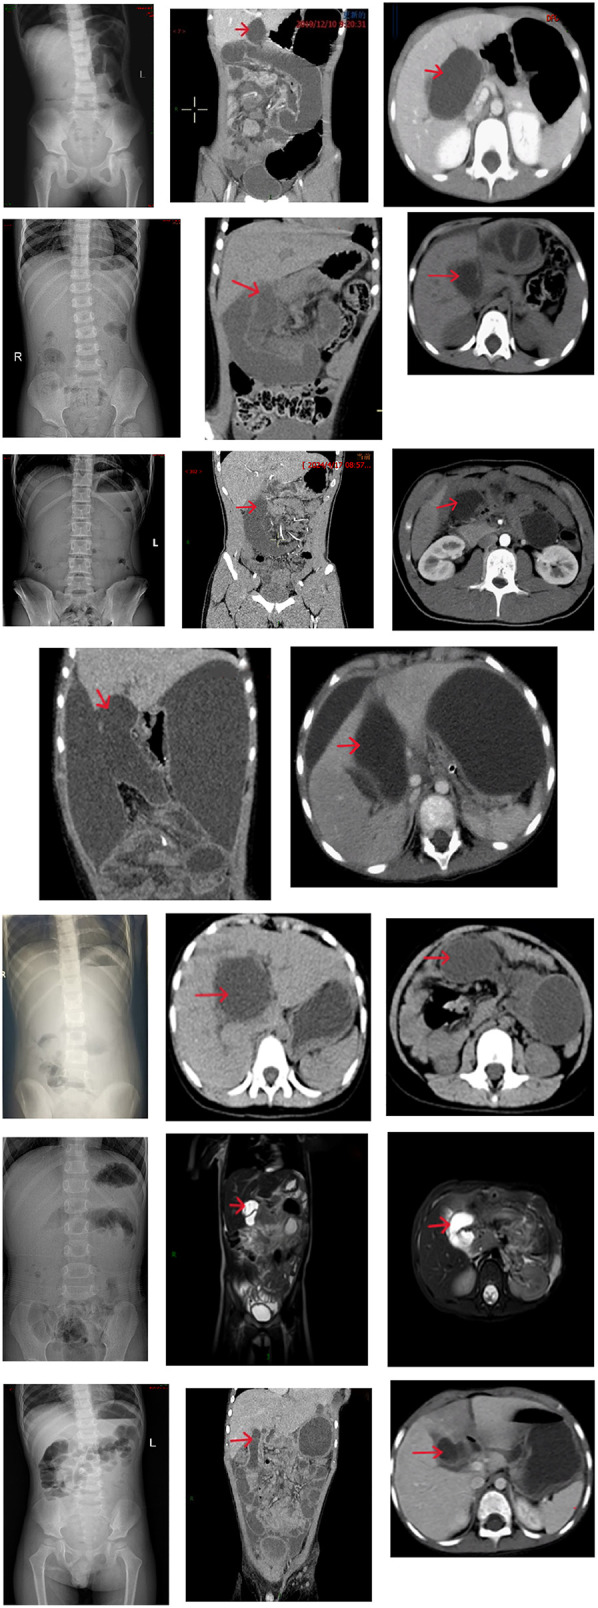

Preoperative laboratory and imaging data are summarized in Table 3. Two patients demonstrated conjugated hyperbilirubinemia on serial liver function. Abdominal x-ray in the standing position showed decreased bowel gas or small air-fluid levels in 8 patients. Abdominal CT or MRI revealed signs of bowel obstruction, volvulus, internal hernia, and bowel necrosis. In patients diagnosed intraoperatively with internal hernias or bowel volvulus, preoperative CT or MRI identified fluid accumulation in the biliary-jejunal loop at the hepatic hilum, as shown in Figure 2 (cases 1, 3, 5, 6, 7, 8, and 9).

Diagnosis and management principles